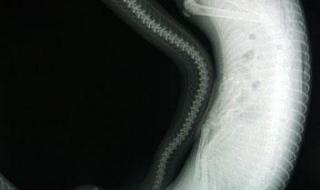

1、北京蟒山因山势起伏如大蟒故名蟒山,其最高峰659米。

2、传说,元朝末年,在蟒山盘踞着一条大蟒蛇,经常危害过路行人,后来来了一位阿訇叫筛海巴巴,他自告奋勇穿上一件缀满刀子的衣服,一下钻进大蟒的肚子里把大蟒杀死了,筛海巴巴不久也死了,就埋在昌平男邵乡何营村,现在那里还有他的墓和祠堂。人们为纪念筛海巴巴,便称此山为蟒山。